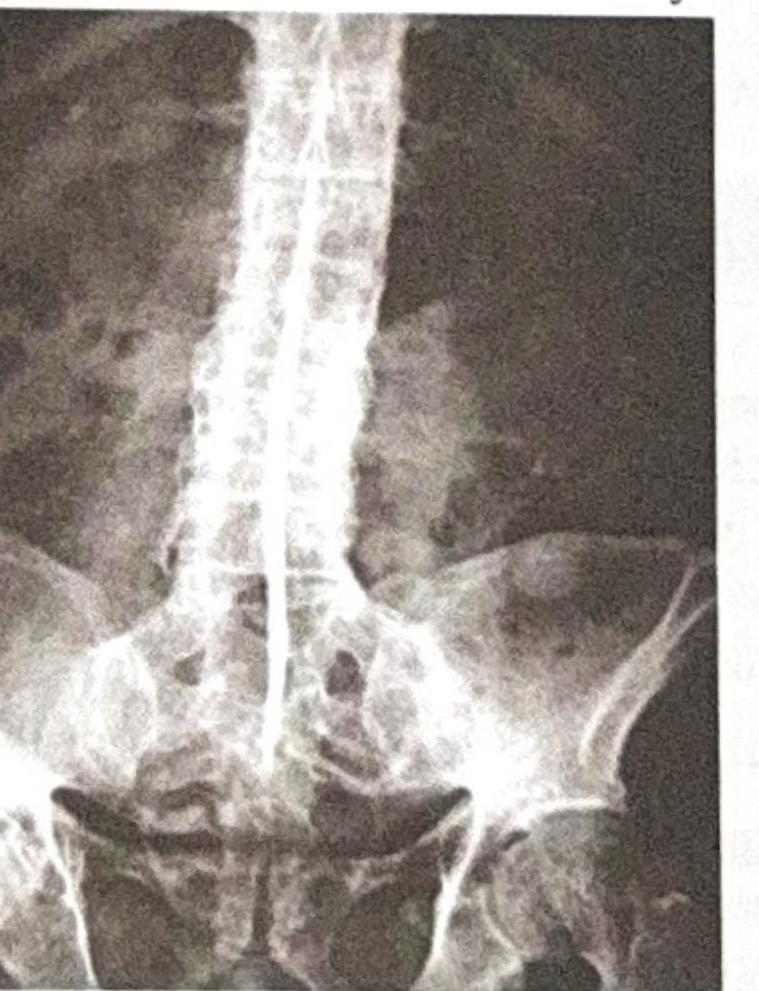

A 50-year-old male presents with backache, morning stiffness, red eye, and ankle swelling. Based on the X-ray provided, what is the most likely diagnosis?

A 26-year-old male presents with backache, morning stiffness, reduced chest expansion, and reddening of the eyes. The X-ray provided is shown below. What is the most likely diagnosis?

A young male presents with acute redness of the eye. His X-ray of the spine is shown below. What is the most likely condition?

Explanation: ***Ankylosing Spondylitis*** - The X-ray likely shows features of **sacroiliitis** (joint space narrowing, sclerosis, erosion) and possibly **vertebral fusion**, consistent with ankylosing spondylitis. The clinical presentation of **backache, morning stiffness, red eye (uveitis), and ankle swelling (enthesitis)** are classic extra-articular manifestations and peripheral arthritis of ankylosing spondylitis. - X-ray findings like **bamboo spine** (late stage), syndesmophytes, and erosions of the sacroiliac joints are characteristic of this seronegative spondyloarthropathy. *Paget's Disease* - Paget's disease is characterized by disorganized bone remodeling, leading to bone enlargement, deformity, and increased density or lysis. It typically does not present with **sacroiliitis** or widespread **ankylosis**. - Clinical features usually include **bone pain**, **bone deformities**, and potentially **nerve compression**, which are not the primary symptoms described. *Healed TB spine* - Healed TB spine (Pott's disease) would typically show bone destruction, collapse of vertebral bodies, **kyphosis**, and often calcified abscesses. - While backache can occur, the presence of **red eye** and **ankle swelling** are not characteristic of spinal tuberculosis. *Osteopetrosis* - Osteopetrosis is a rare genetic disorder characterized by **increased bone density** due to defective osteoclast function, leading to abnormally thick and brittle bones. - The X-ray would show **generalized sclerosis** (diffuse increased bone density) throughout the skeleton, which is not the primary finding indicated by the clinical context of sacroiliitis and joint fusion.

Explanation: ***Ankylosing spondylitis*** - The patient's symptoms of **backache, morning stiffness, reduced chest expansion**, and **reddening of the eyes** (uveitis) are classic manifestations of ankylosing spondylitis. The X-ray image (though somewhat obscured) shows signs consistent with **sacroiliitis** and possibly early **syndesmophyte formation**, leading to a "bamboo spine" appearance which is pathognomonic. - This condition is a **chronic inflammatory disease** primarily affecting the spine and sacroiliac joints, more common in young men. *Osteopetrosis* - This is a rare genetic disorder characterized by **increased bone density** due to defective osteoclast function, leading to bone fragility. - Clinical features usually include **fractures**, cranial nerve palsies due to narrowed foramina, and **hematologic abnormalities** due to marrow obliteration, not inflammatory back pain or uveitis. *Paget's disease* - **Paget's disease of bone** involves localized areas of excessive bone turnover, leading to disorganized bone structure. - It typically affects older individuals and presents with **bone pain**, skull enlargement, and hearing loss, rather than inflammatory back pain and uveitis in a young male. *Rheumatoid arthritis* - Rheumatoid arthritis is a **chronic autoimmune disease** primarily affecting the **synovial joints**, mostly small joints, symmetrically. - While it can cause systemic inflammation, it typically spares the axial skeleton, and symptoms like severe morning stiffness and reduced chest expansion with specific X-ray findings described are not characteristic.

Explanation: ***Ankylosing Spondylitis*** - The young male presenting with **acute redness of the eye** (uveitis) and a spinal X-ray showing changes consistent with **bamboo spine** (fusion of vertebrae due to syndesmophyte formation) is highly indicative of ankylosing spondylitis. - This condition is a chronic inflammatory disorder primarily affecting the **axial skeleton** (spine and sacroiliac joints) and is often associated with extra-articular manifestations like **uveitis**. *Psoriatic Arthritis* - While psoriatic arthritis can affect the spine and cause uveitis, the characteristic imaging findings in the provided X-ray, particularly the **bamboo spine**, are more classical for ankylosing spondylitis. - Psoriatic spondylitis often presents with more asymmetric and less diffuse spinal involvement compared to ankylosing spondylitis. *Rheumatoid Arthritis* - Rheumatoid arthritis primarily affects the **peripheral joints** (e.g., small joints of hands and feet) and typically spares the axial skeleton, except for involvement of the **cervical spine**. - **Uveitis** is a rare extra-articular manifestation in rheumatoid arthritis, and the X-ray findings are not typical for this condition. *Sjögren Syndrome* - Sjögren syndrome is a chronic autoimmune disease characterized by **dry eyes** (keratoconjunctivitis sicca) and **dry mouth** (xerostomia) due to lymphocytic infiltration of exocrine glands. - While it can cause some joint pain, it does not typically lead to the characteristic spinal changes seen on the X-ray or acute uveitis.